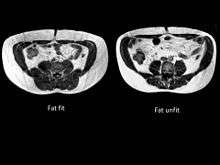

To classify an individual as TOFI, it is essential to measure their internal fat content. The only way that this is possible is by using magnetic resonance Imaging (MRI) or CT scanning. The parameters of the MRI scanner are manipulated to show fat as bright (white) and lean tissue as dark.

The figure clearly shows that despite having an identical waist circumference (in this example all men had a waist of 84 cm), there is considerable variation in the amount of visceral fat (volumes shown on the image in litres) present.

No less important than the TOFI are the metabolic opposites. The subjects have variously been described as being 'FOTI' (fat outside, thin inside), the “metabolically healthy obese” (MHO)[6][7][8][9] or even the fit fat.[10][11] These subjects have little internal fat relative to their size and an example of this can be seen in the figure where MRI images taken at the level of the umbilicus are shown from a fat-fit (FOTI) and a fat-unfit (control) subject.